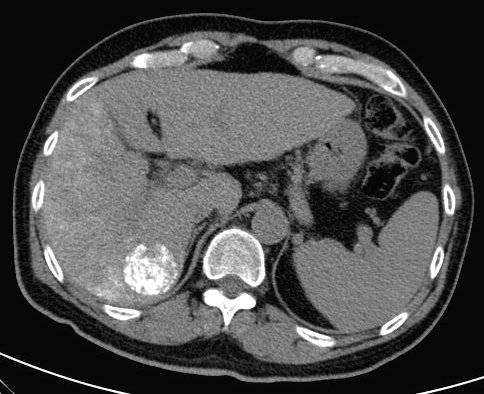

19.3.2. Chemoembolization

TAE (Transcatheter Arterial Embolization) and TACE (Transcatheter Arterial ChemoEmbolization) are methods with which the supplying artery/arteries of the tumor are selectively approached through the branches of the hepatic artery. When the catheter is in position the tumor branches are injected with a special, oily contrast material, Lipiodol (TAE). The injected material is used as an embolization material (figure 18.), other chemotherapeutical drugs (5-Fluoro-Uracil, Epirubicin, Cisplatin, Mytomicin-C) can also be used (TACE) (figure 19.).

Image

Figure 18. – Lipiodol uptake in HCC, selective catherarization, injection of 10 ml Lipiodol (DSA)

Figure 19. – TACE, CT control (2 weeks after treatment)

Compared to systemic chemotherapy, with these methods 10 or even 100 times greater drug concentrations can be delivered to the tumor tissue. Moreover, due to the effects of Lipiodol, the drug effects persist longer, while normal liver parenchyma will wash out the chemicals faster leaving little or no harm.

This can be successfully combined with the other percutaneous methods, especially during the treatment of multiplex primary and secondary tumors.